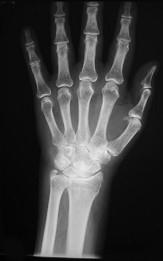

类风湿手X线(如图)的特点是 ( )A、软组织肿胀,关节变形B、关节游离体C、骨质硬化及增生D、骨质疏松E、关节间隙狭窄

问题 类风湿手X线(如图)的特点是 ( )

选项 A、软组织肿胀,关节变形 B、关节游离体 C、骨质硬化及增生 D、骨质疏松 E、关节间隙狭窄

答案 ADE